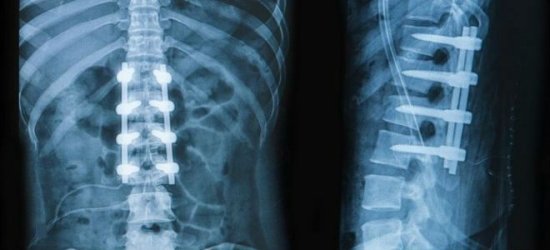

Почему болит низ спины, может установить только врач. Ни в коем случае не следует заниматься самодиагностикой и самолечением. Диагноз ставится на основании жалоб больного, клинических проявлений, анамнестических данных, результатов инструментальных методов исследования. Пациенту назначают рентгенографию, миелографию, МРТ, КТ и другие виды обследований.

Компьютерная томография является эффективным и высокоинформативным способом выявления различных структурных изменений в позвоночнике, вызванных травматизацией, инфекционным процессом, опухолевыми образованиями, остеопорозом и другими заболеваниями. В основе миелографии лежит применение контрастирующего вещества. Метод применяют при подозрении на стеноз позвоночного канала, грыжевых образованиях, опухолях и других патологических процессах в позвоночнике.